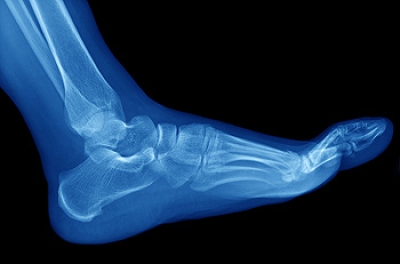

Dr. Kenneth Williams is a board-certified podiatrist with over three decades of experience. He is known to be thorough, and will always try to treat his patients conservatively. He has helped patients with all kinds of foot and ankle conditions, such as: foot pain, plantar fasciitis and other forms of heel pain, ingrown toenails, diabetic foot care and limb salvage, and more. As a highly skilled podiatric surgeon, Dr. Williams offers surgical solutions when necessary, such as advanced minimally invasive surgery (MIS) for the correction of painful bunions.

Dr. Williams also uses the JM Orthotics Heat Moldable system to create custom orthotic devices to help reduce pain and increase mobility in a variety of issues.